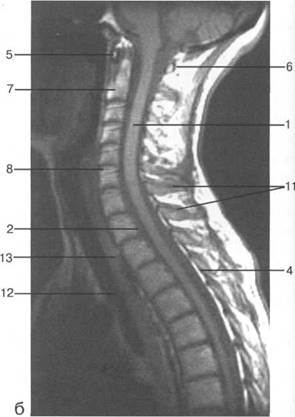

К моменту рождения (рис. 3.1) тело позвонка почти полностью состоит из к 141s183b 86;стной ткани, за исключением лимбусов, которые остаются хрящевыми. Дуга представлена двумя половинами, не слившимися ни с телом позвонка, ни между собой. Суставные отростки сохраняют перифе

MPT. Cw_v.

V2; Th,; Thn;